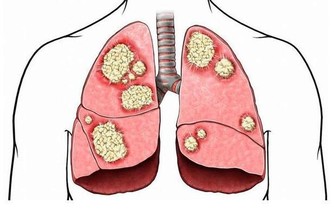

1、觀察自己的雙手,如果發現指尖比指節更粗大,可能是患有較嚴重的肺部疾病;